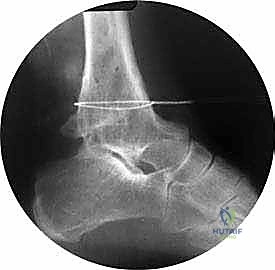

TECH FIG 2A: Lateral intraoperative radiographic view showing the Gigli saw passed at the level of the ankle malunion.